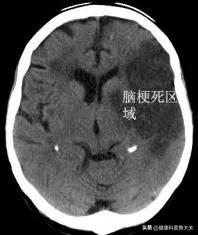

2.infarctus cérébralL'infarctus cérébral est un état dans lequel l'irrigation sanguine du cerveau est altérée pour diverses raisons, entraînant une ischémie, une hypoxie et une nécrose du tissu cérébral et provoquant un dysfonctionnement des zones d'irrigation sanguine correspondantes. Outre les facteurs incontrôlables tels que l'âge, le sexe et la famille, il existe de nombreuses causes communes contrôlables d'infarctus cérébral, telles que l'hypertension, l'hyperlipidémie, l'hyperglycémie, le tabagisme, l'alcoolisme, la fibrillation auriculaire et les maladies coronariennes. Hyperhomocystéinémie. Sténose carotidienne asymptomatique, inactivité physique et obésité.

La question posée par le sujet peut recevoir une réponse sans équivoque, mais pas nécessairement. La situation est différente d'une personne à l'autre, pourquoi est-elle différente d'une personne à l'autre ? L'infarctus cérébral est une occlusion des vaisseaux sanguins cérébraux causée par la mort des cellules du cerveau.

L'occlusion des vaisseaux sanguins cérébraux se développe principalement sur la base d'un apport sanguin cérébral insuffisant, qui est une maladie chronique, et l'infarctus cérébral est l'expression aiguë de cette maladie chronique.